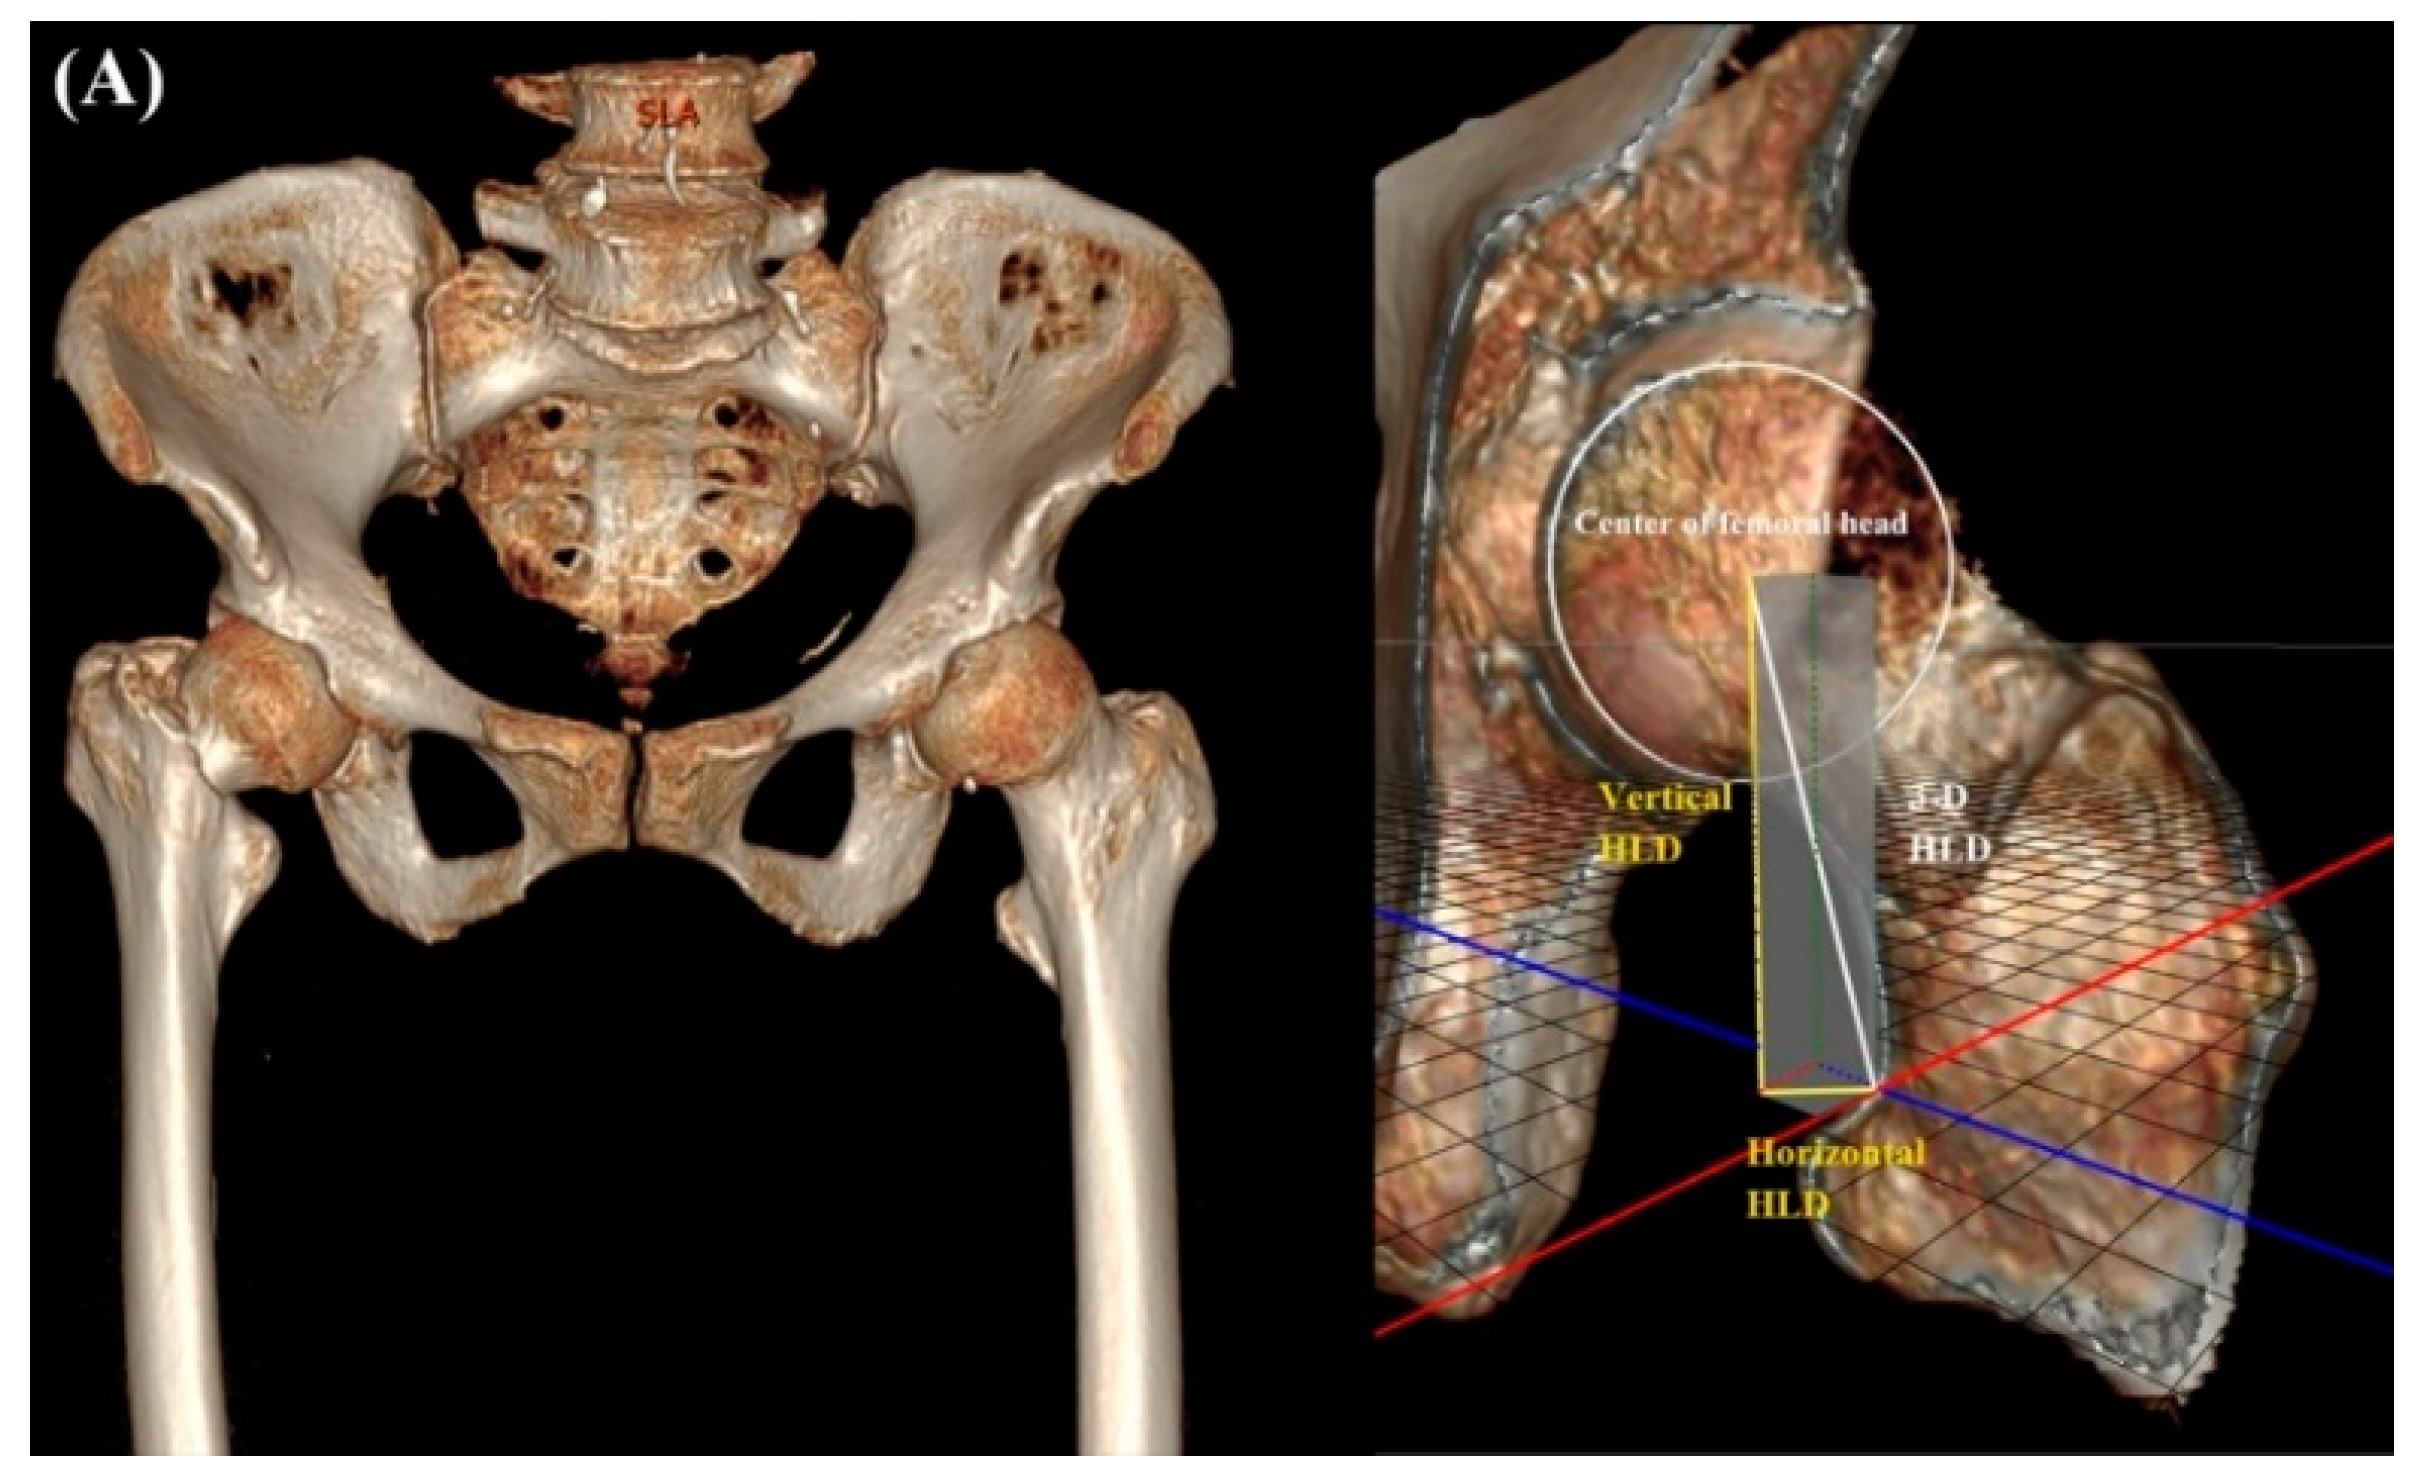

2.2. Radiologic Parameters

| 3-D HLD | - | 45.9 ± 3.6 | N/A |